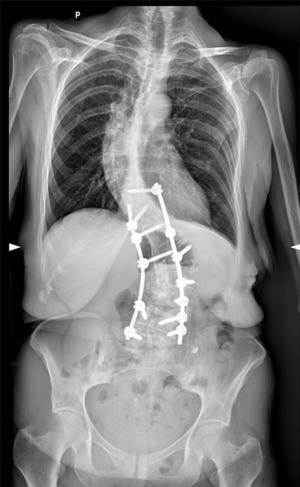

At 3-month post-surgery check-up, X-rays revealed that the spinal instrumentation had dislodged secondary to osteopenia and torsional forces. The left Co-Cr rod, due to its stiffness, which is higher than the titanium rod, was carrying higher forces onto the screws, which pulled the screws from L4 and L3 out of the pedicles (Figure 3). Revision surgery was performed, the loose screws were taken out and replaced in L4 and L5, and a new titanium rod was placed on this side. Cobb’s angle decreased to 42° after the surgery (Figures 4,5). The patient was discharged as no complications occurred.

At follow-up a month after the revision surgery, radiographs showed spinal instrumentation intact. The patient reported that the pain subsided and she no longer had radiating pain to the leg. Her mobility and gait have improved greatly, and she was able to return to work.

A follow-up three months post-revision surgery showed significant improvement. The patient reported no pain at rest and a 2/10 VAS while walking with no radiating pain. She stopped taking opioids and remained only on gabapentin. The patient was very satisfied with the results and was now waiting to start physiotherapy.

At a follow-up nine months post-revision surgery, the patient’s symptoms were stable with no pain at rest and a 2/10 VAS while walking without radiating pain. X-rays revealed the spinal instrumentation to be intact. We’re planning to follow-up with the patient in 6–8 months to monitor her condition.